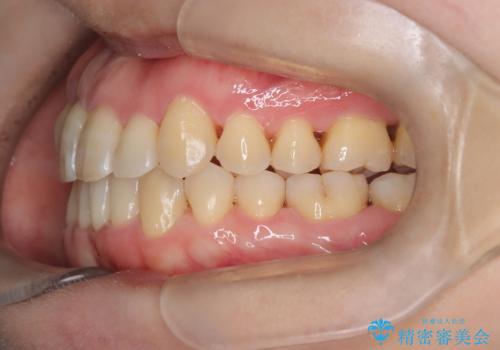

【インビザライン】ずれた前歯の噛み合わせをなおしたい

- 前歯の噛み合わせが悪いことを主訴に来院されました。

歯周病も併発していたため、歯牙への負担が少なくなるように治療計画をたて、インビザラインにて治療を完了しました。

矯正開始前に半年間、歯周治療を行ってからインビザラインを装着しています。